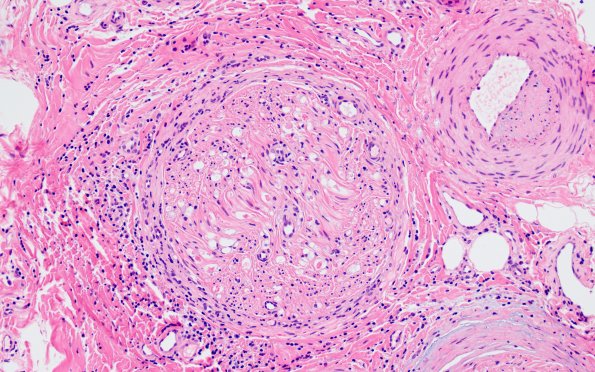

Washington University Experience | PERIPHERAL NEUROPATHY | 9B PERINEURITIS & PERINEURIAL PATHOLOGY | 1A5 Epineuritis & Perineuritis (Case 1) Immune checkpoint 20X

Occasional endoneurial blood vessels show plump endothelial cells with prominent nucleoli, consistent with focal reactive changes. (H&E)